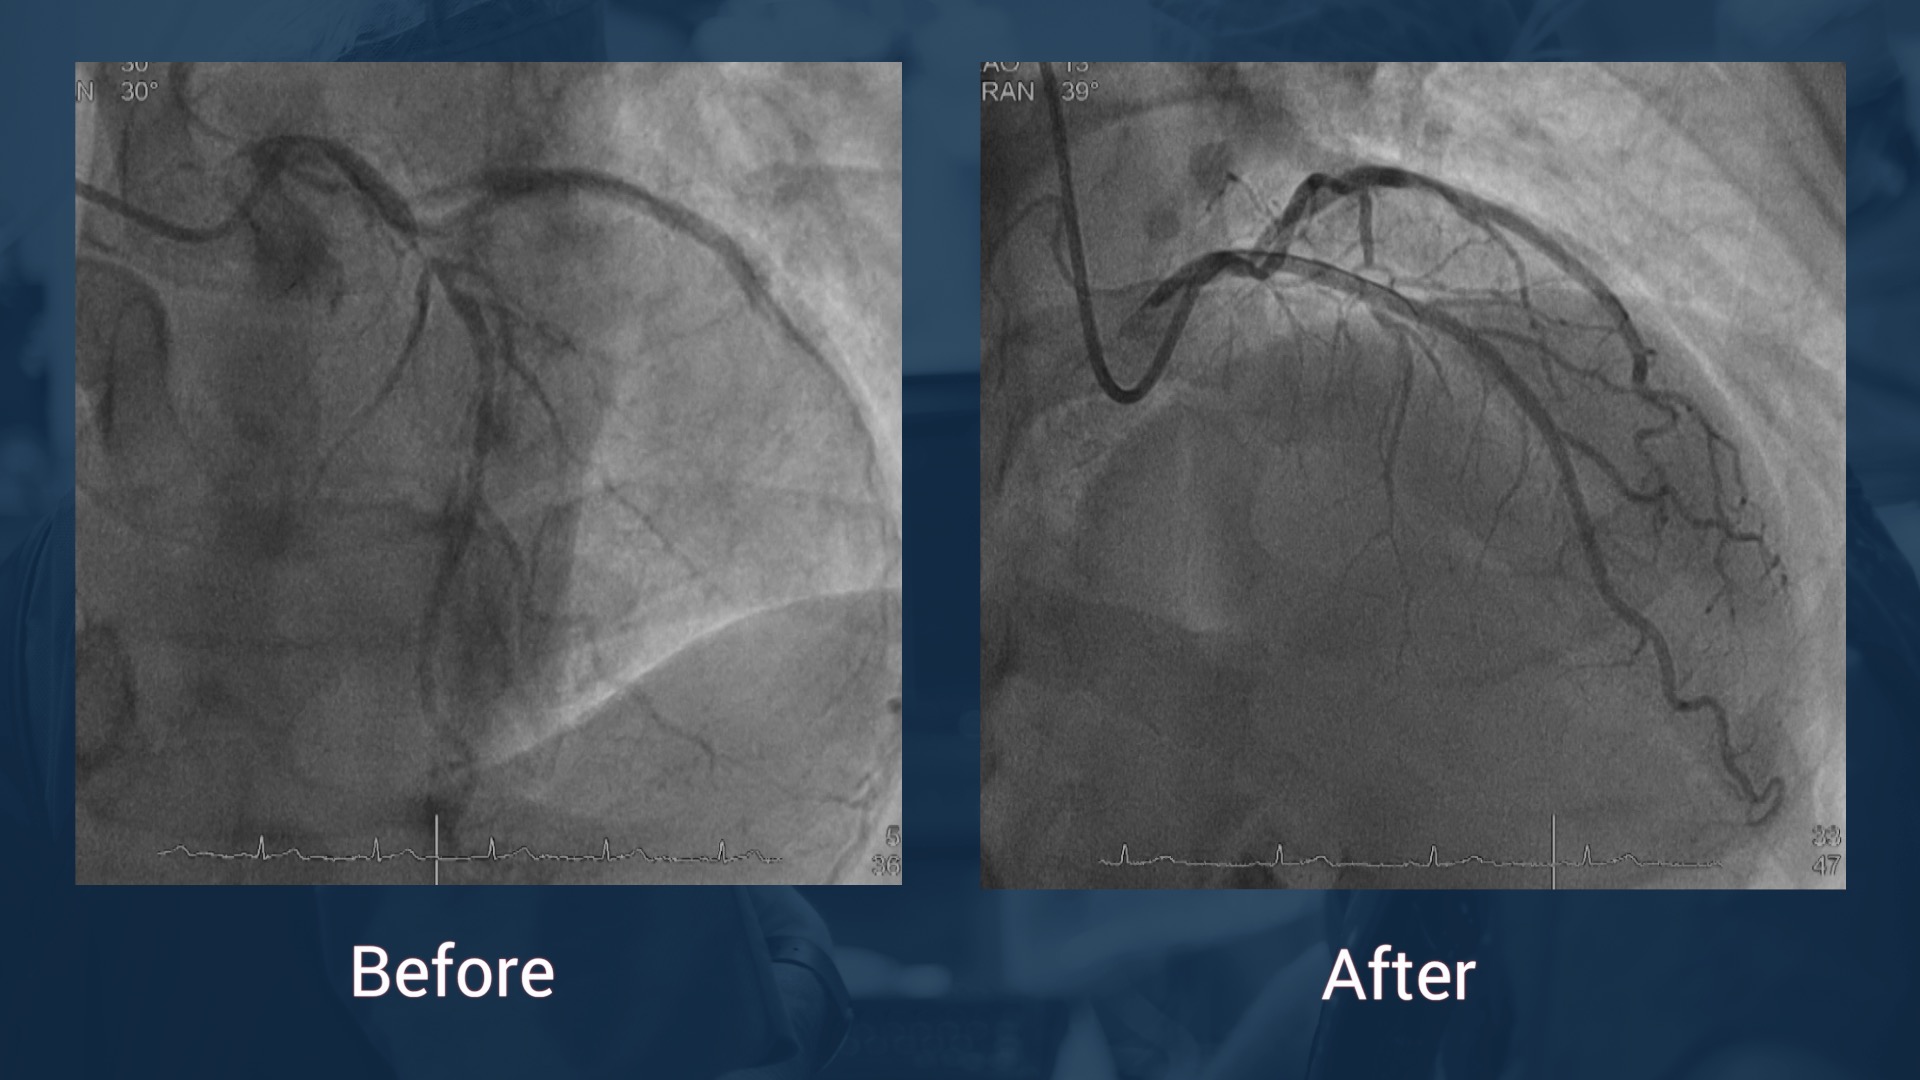

2013 CTO PCI of the RCA with 4 DES (Xience) for angina

CAG 14.7.17: LAD without stenosis, CX without stenosis, in-stent reocclusion of the RCA